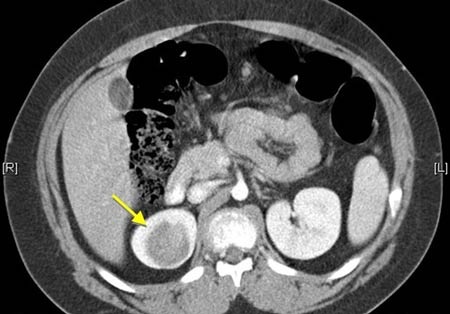

Khối u Wilms là khối u ở thận: có khoảng 7,5% trẻ em mắc bệnh sẽ phát triển u này. Do các khối u tăng trưởng nên trẻ cần được siêu âm bụng hoặc chụp cộng hưởng từ (MRI) 3 tháng/lần cho đến khi trẻ được 7 - 8 tuổi. Tuy nhiên, các khối u giảm dần và thường không phải là vấn đề đáng lo ngại sau khi trẻ 8 tuổi. Tiến sĩ Beckwith khuyên rằng: đứa trẻ nào có anh hoặc chị có một hoặc hai trong số các triệu chứng của hội chứng Beckwith-Wiedemann thì đứa trẻ đó cũng nên kiểm tra siêu âm 3 tháng/lần.

Hình ảnh khối u Wilms trên phim chụp cắt lớp.